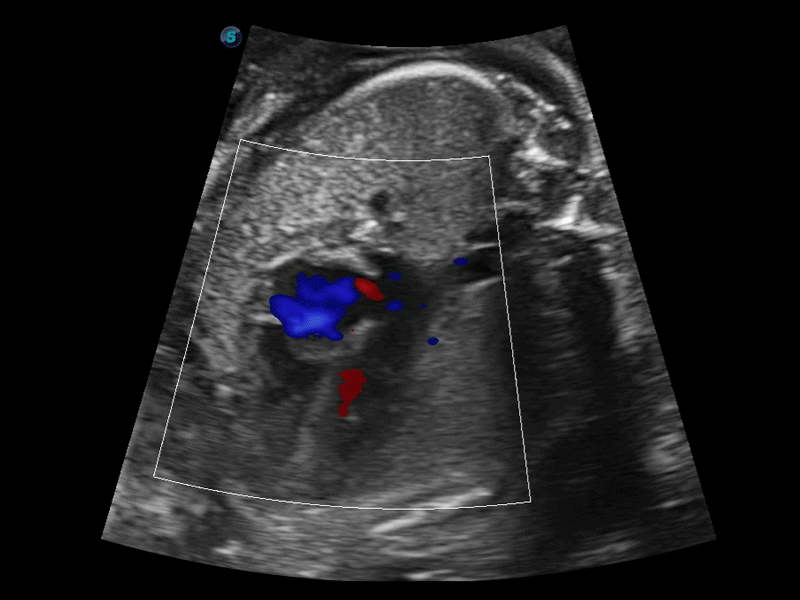

相控阵探头

凭借狗万官方网站先进的成像技术和优异的探头技术提供的清晰的图像表现,您可以更自信地做出临床决策。